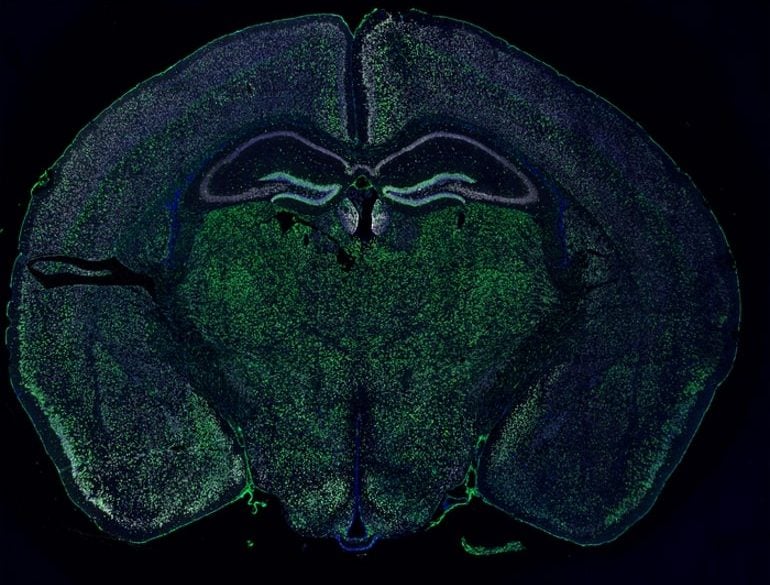

This shows a brain slice

How Some Brain Cells Transfer Material to Neurons in Mice

Study reveals how oligodendrocyte-lineage cells transfer cell material to neurons in mouse brains. The new understanding opens the door for the development of novel therapies for a range of neurodegenerative disorders.